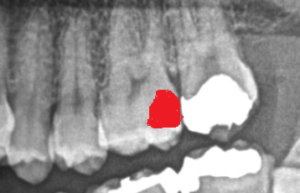

赤い部分が虫歯です。